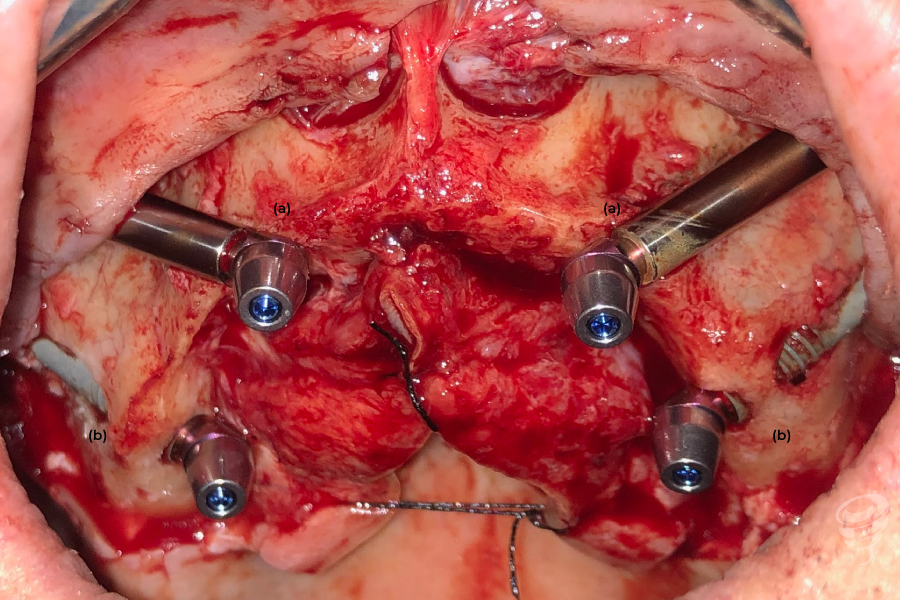

La evolución técnica ha permitido reducir el número de complicaciones, particularmente la aparición de sinusitis, al pasar de la técnica intrasinusal original de Branëmark a técnicas extrasinusales o incluso extramaxilares (imagen 3), donde el implante no tienen ningún contacto con el seno maxilar, permitiendo además adaptarnos a la anatomía específica de cada paciente.

- (a) – Implantes extramaxilares, con anclaje exclusivo en el malar, sin anclaje en la cresta maxilar. (Imagen 3)

- (b) – Implantes extrasinusales, con anclaje en la cresta ósea residual (anclaje maxilar y malar). (Imagen 3)

Imagen 3